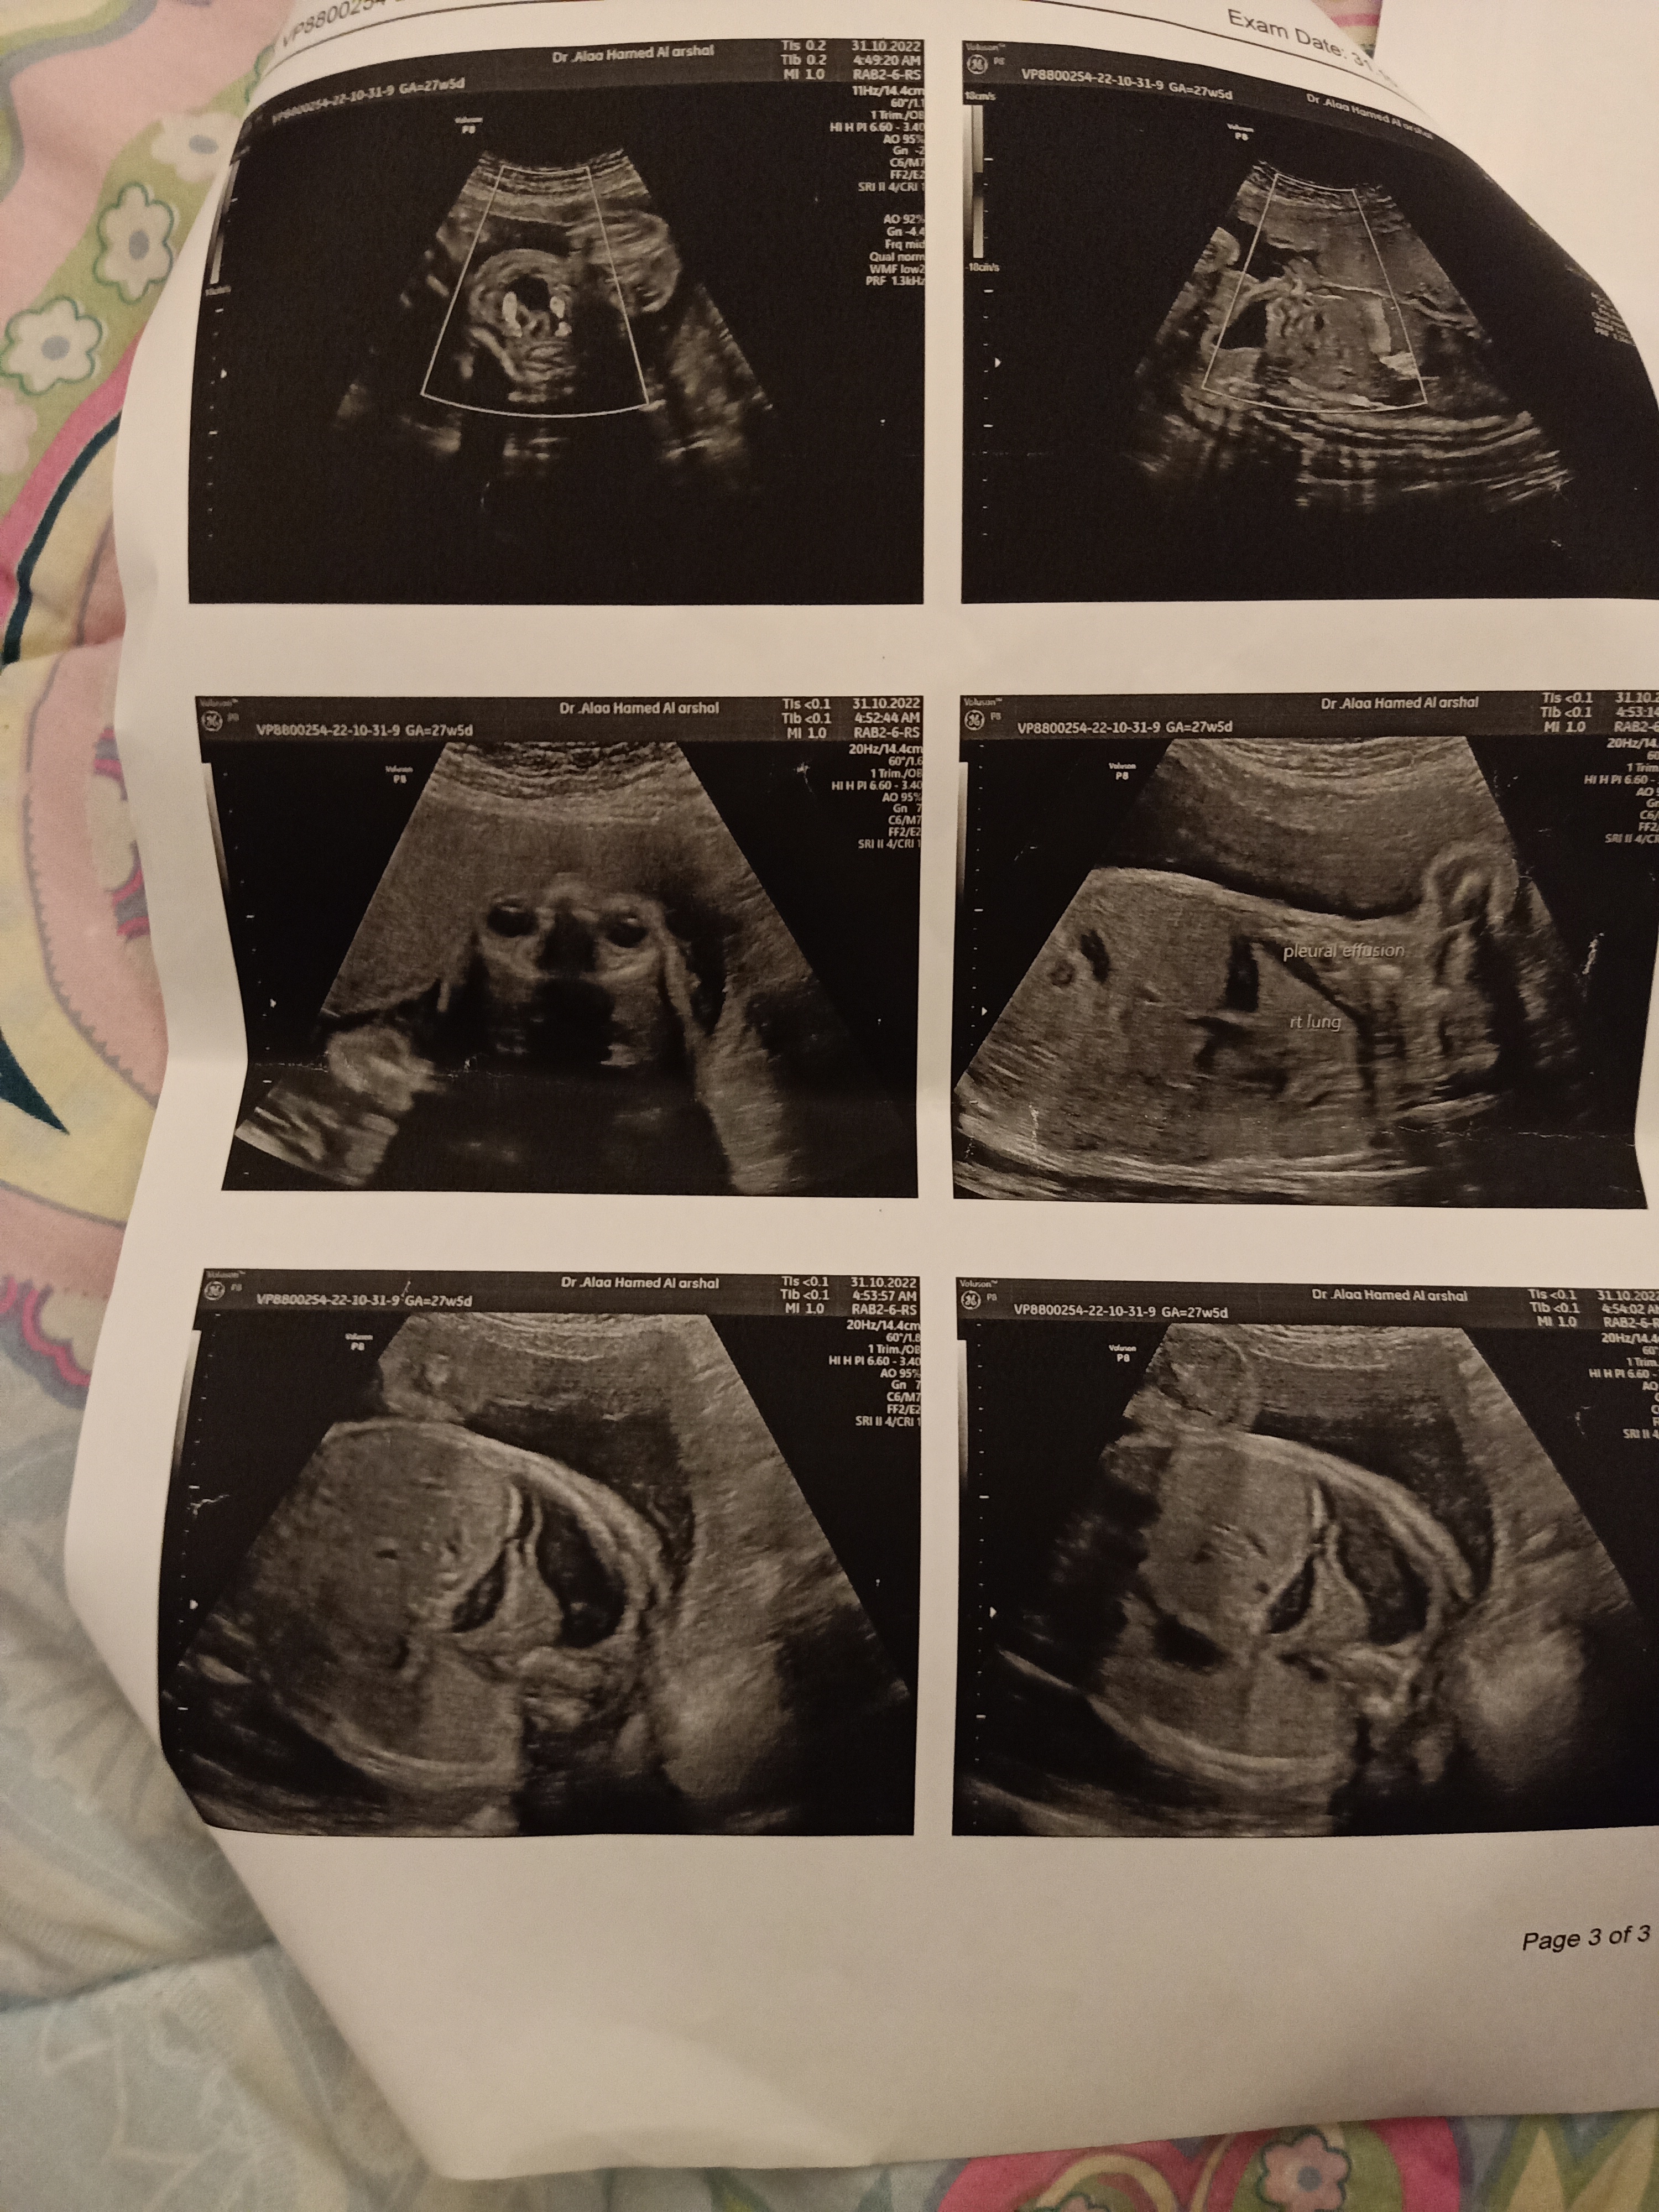

آخر دورة ٢٠/٤ انا حامل بالشهر السابع وجود مياه علي رئة الجنين ممكن تطمني يا دكتورة الاشعه وتطمني أنه طفل...